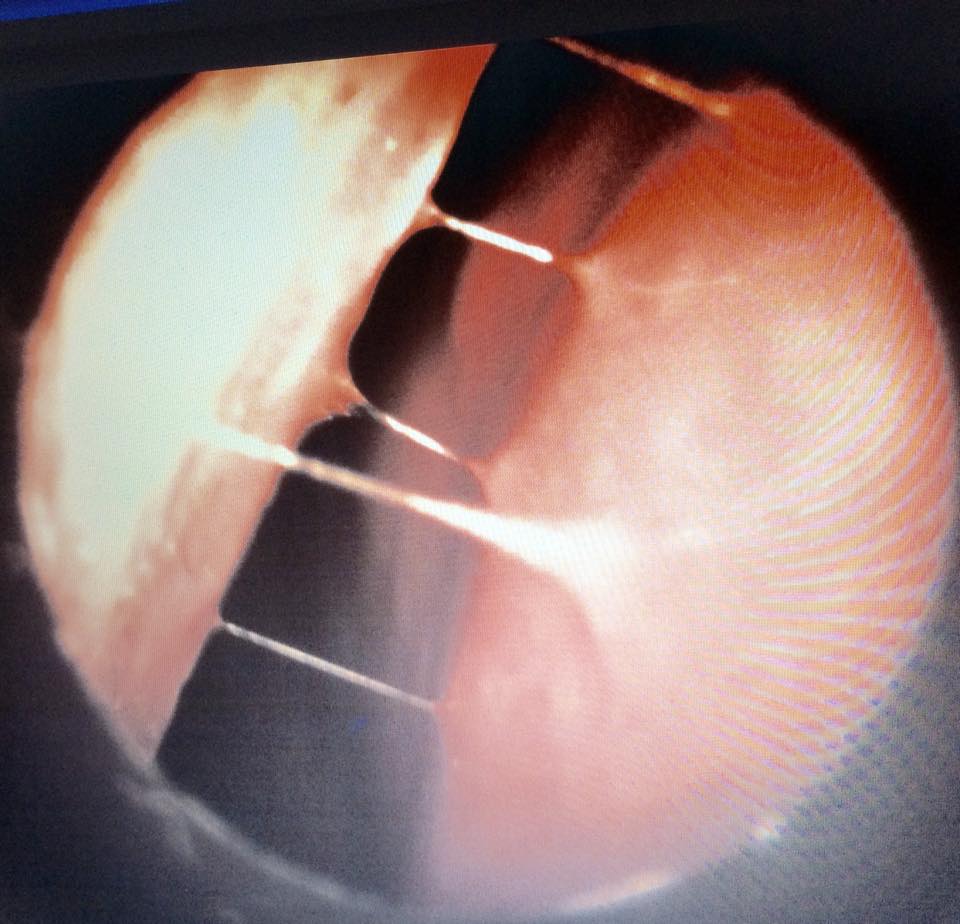

การส่องกล้องและถ่ายภาพให้เห็นบนจอ ใช้เวลาไม่นาน ไม่เจ็บ สามารถส่องในคนไข้เด็กได้

สามารถบอกได้ว่า: จมูกบวมมาก? มีน้ำมูกเหนียว? มีเลือดออก? มีหนองจากไซนัส? มีริดสีดวงจมูก? ผนังจมูกเบี้ยว?

แสดงให้คนไข้เห็น อธิบายให้เข้าใจสาเหตุ ตรวจหาโรคร่วมอื่นๆ และร่วมกันวางแผนการรักษาได้ดีขึ้น